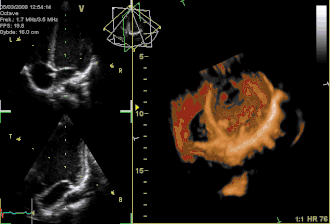

Three-dimensional echocardiogram of a heart viewed from the apex

Three-dimensional echocardiography (also known as four-dimensional echocardiography when the picture is moving) is now possible, using a matrix array ultrasound probe and an appropriate processing system. This enables detailed anatomical assessment of cardiac pathology, particularly valvular defects,[11] and cardiomyopathies.[12] The ability to slice the virtual heart in infinite planes in an anatomically appropriate manner and to reconstruct three-dimensional images of anatomic structures make it unique for the understanding of the congenitally malformed heart.[13] Real-time three-dimensional echocardiography can be used to guide the location of bioptomes during right ventricular endomyocardial biopsies, placement of catheter-delivered valvular devices, and in many other intraoperative assessments.[14]

Three-dimensional echocardiography technology may feature anatomical intelligence, or the use of organ-modeling technology, to automatically identify anatomy based on generic models. All generic models refer to a dataset of anatomical information that uniquely adapts to variability in patient anatomy to perform specific tasks. Built on feature recognition and segmentation algorithms, this technology can provide patient-specific three-dimensional modeling of the heart and other aspects of the anatomy, including the brain, lungs, liver, kidneys, rib cage, and vertebral column.[15]